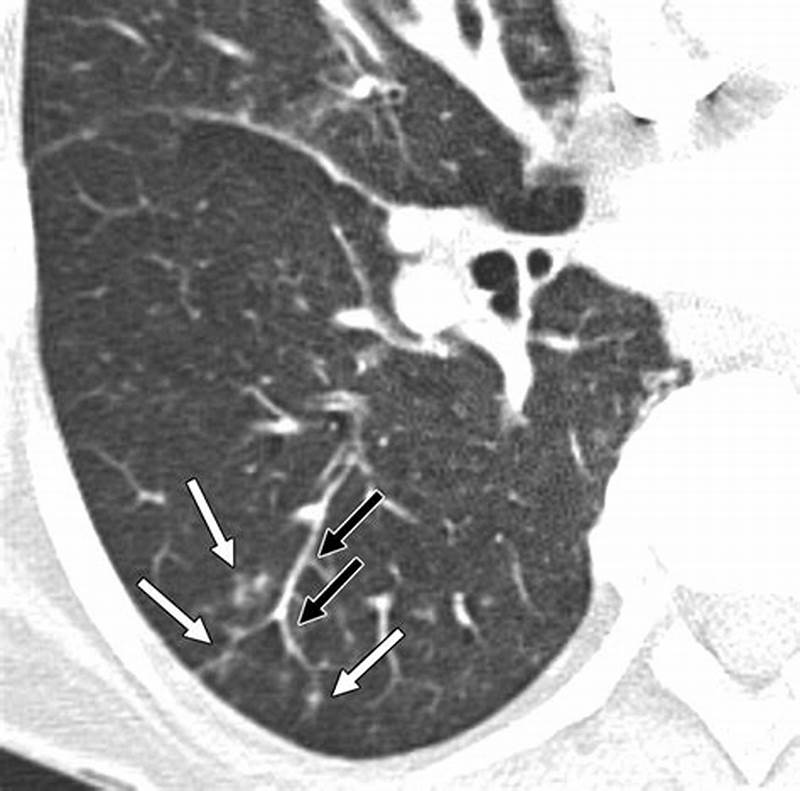

Tree Bud Pattern